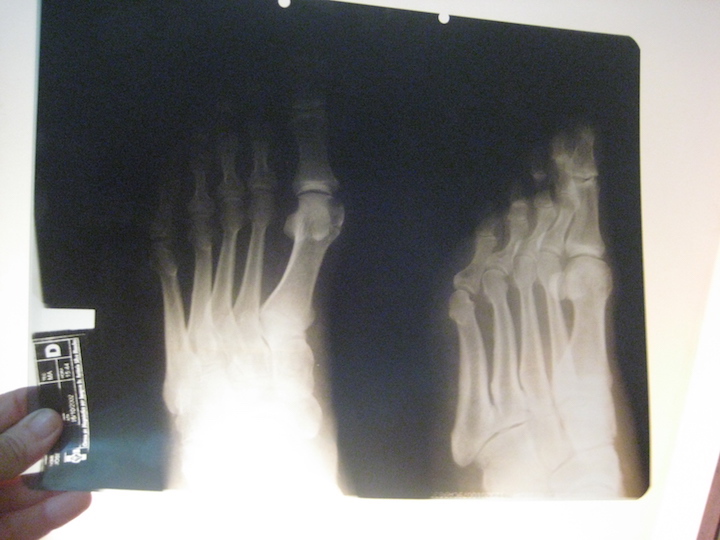

Na chapa de radiografia, a parte mais escura, são grãos de prata (pode se dizer que cada 10 chapas grandes podem conter 1g de prata) e o processo de reciclagem consiste em separar a prata do plástico (acetato).